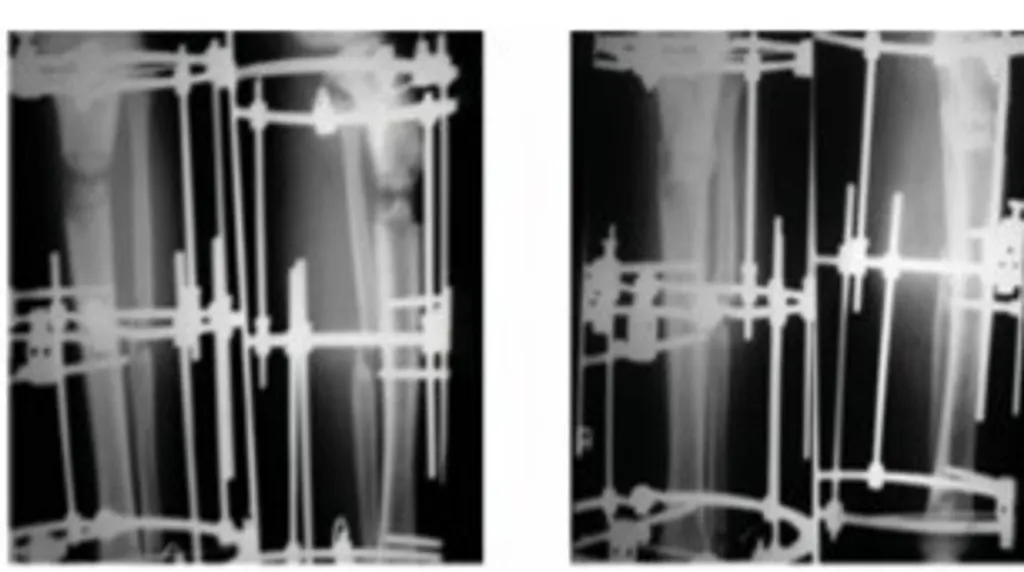

രണ്ടാമത്തെ രോഗി 13 വയസ്സുള്ള ഒരു പെൺകുട്ടിയായിരുന്നു. ഇരുകാലുകളിലും അതിതീവ്രമായ വളവ് ഉണ്ടായിരുന്ന അവൾ, പല സ്ഥലങ്ങളിൽ ചികിത്സ തേടിയിരുന്നു. (Fig 10 a,b,c,d,e,f) വിശദമായ പരിശോധനയിൽ അവൾക്ക് റീനൽ റിക്കറ്റ്സ് എന്ന രോഗമാണെന്ന് കണ്ടെത്തി.

റീനൽ റിക്കറ്റ്സിന്റെ പ്രധാന പ്രശ്നം അസ്ഥിയുടെ ഗുണമേന്മ കുറയുന്നതാണ്. അസ്ഥി മൃദുവാകുകയും ധാതുവൽക്കരണം (Mineralization) ശരിയായി നടക്കാതിരിക്കുകയും ചെയ്യുന്നു. അതിനാൽ ശസ്ത്രക്രിയയ്ക്ക് മുമ്പ് അസ്ഥിയുടെ ഗുണമേന്മ മെച്ചപ്പെടുത്തേണ്ടത് അനിവാര്യമാണ്.

അസ്ഥിയുടെ അവസ്ഥ മെച്ചപ്പെടുത്തിയതിന് ശേഷം ഇലിസാരോവ് ഫ്രെയിം ഉപയോഗിച്ച് ചികിത്സ ആരംഭിച്ചു (Fig 11 a,b,c,d). ഇത് വളരെ സങ്കീർണ്ണമായ വൈകല്യമായതിനാൽ, സാധാരണ ഇലിസാരോവ് സംവിധാനത്തോടൊപ്പം സിക്‌സ്-ആക്സിസ് (Six-axis) കറക്ഷൻ സിസ്റ്റം ഉപയോഗിച്ചു. ഇന്ത്യയിൽ ഇത്തരം നിരവധി സിക്‌സ്-ആക്സിസ് സംവിധാനങ്ങൾ ലഭ്യമാണ്. ഇവിടെ ജർമൻ നിർമ്മിതമായ ‘ഹെക്സാപോഡ്’ (Hexapod) എന്ന കമ്പ്യൂട്ടറൈസ്ഡ് സംവിധാനം ഉപയോഗിച്ചു.

ഇലിസാരോവ് ഫ്രെയിം ഘടിപ്പിച്ചതിന് ശേഷം, ഹെക്സാപോഡ് സിസ്റ്റം ഫ്രെയിമിൽ ബന്ധിപ്പിച്ചു. കോർത്തിക്കോട്ടമി ചെയ്ത ശേഷം എടുത്ത എക്സ്-റേ ചിത്രങ്ങൾ സോഫ്റ്റ്‌വെയറിലേക്ക് നൽകി, വൈകല്യം ക്രമാനുസൃതമായി ശരിയാക്കാനുള്ള ഷെഡ്യൂൾ തയ്യാറാക്കി. സോഫ്റ്റ്‌വെയർ നിർദ്ദേശിക്കുന്നതനുസരിച്ച് ഫ്രെയിമിലെ നട്ടുകൾ തിരിച്ച് വൈകല്യം പതുക്കെ ശരിയാക്കി.

അസ്ഥിയുടെ അവസ്ഥ മെച്ചപ്പെടുത്തിയതിന് ശേഷം ഇലിസാരോവ് ഫ്രെയിം ഉപയോഗിച്ച് ചികിത്സ ആരംഭിച്ചു (Fig 11 a,b,c,d).

ഇരുകാലുകളിലെയും തുടയെല്ലുകളും കാൽഎല്ലുകളും ഇതേ രീതിയിൽ നേരെയാക്കി. തുടർന്ന് കുറച്ച് ആഴ്ചകൾ ഫിസിയോതെറാപ്പി നൽകിയതോടെ, കുട്ടിക്ക് പൂർണ്ണമായും വൈകല്യങ്ങളിൽ നിന്ന് മോചനം ലഭിച്ചു (Fig 12 a,b,c).